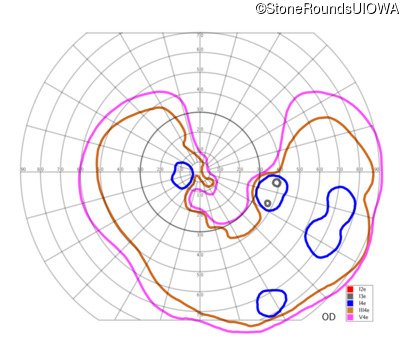

This 47 year old woman was born with a supernumerary digit on the ulnar side of both hands. As a young child, her best corrected visual acuity was completely normal. She had no difficulties with her vision until age 30 when her visual acuity could no longer be corrected to 20/20 and she began to notice some night blindness.

The clinical features supporting the diagnosis of Bardet Biedl syndrome in this patient include: bone-spicule-like pigmentation, narrowed arterioles and macular atrophy on ophthalmoscopy; photoreceptor loss on OCT; ulnar polydactyly, obesity, abnormal cognition, hypertension; and, normally sighted parents.